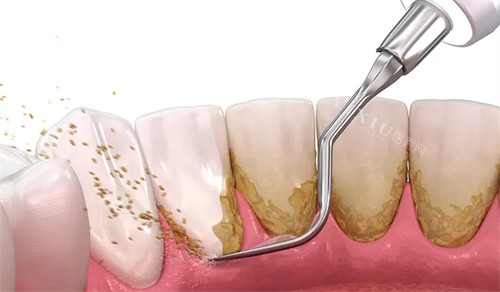

技术比较靠前:科室配备智能化口腔CT、3D打印种植导板等新型设备,实现精细诊疗。例如,种植牙手术采用小创口技术,创口小、改善快,患者术后满意度达98%。

焦作市第二人民医院口腔科以“正规、便捷、贴心”为服务宗旨,致力于为患者提供高品质口腔诊疗服务。无论是日常洗牙、补牙,还是复杂种植、矫正,科室均能满足需求。患者可通过电话预约、合理安排就诊时间,享受有效、优质的医疗服务。